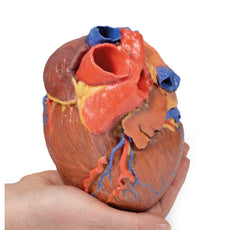

3D Printed Heart internal structures Replica

The anterior wall of the right ventricle has also been removed to expose the right atrioventricular valve and its three cusps (anterior, posterior, and septal), including the chordae tendineae connecting them to respective papillary muscles projecting from trabeculae carneae (including a septomarginal trabecula entering the anterior papillary muscle from the interventricular septum). The smooth wall of the conus arteriosus is also exposed leading to the pulmonary semilunar valve (left, right, and anterior cusps) at the base of the pulmonary trunk. Preserved and encircling the right atrioventricular valve is the right coronary artery, ultimately passing to the posterior aspect and the origin of the posterior interventricular artery and atrioventricular nodal artery.

On the posterior side of heart the terminations of the pulmonary veins are visible entering the opened left atrium. Just anterior to the depression of the fossa ovalis in the interatrial septum the left atrioventricular valve with its two cusps (anterior and posterior) is preserved, along with the associated chordae tendineae and papillary muscles in the ventricle.

The walls of the opened left ventricle preserve well-developed trabeculae carneae. At the apex of the ventricle the aortic semilunar valve (with left, right, and posterior cusps preserved) can be seen at the base of the sectioned aorta alongside the origin of both coronary arteries. The left coronary artery in this specimen is very short, giving rise almost immediately from its origin to the left anterior descending artery, the diagonal artery, the ramus intermedius, and the circumflex branch. The latter branch passes between the left atrium and ventricle adjacent to the opened coronary sinus leading to the right atrium. The left anterior descending branch penetrates the myocardium in this individual and travels through the tissue, only emerging superficially to become visible again near the apex.

3D Printed Heart internal structures replica

This 3D printed heart has been dissected to display the internal structures of the chambers. At the base of the heart the termination of the superior vena cava is preserved entering the right atrium. Part of the inferior vena cava is also preserved on the inferior aspect of the right atrium; however, most of the vessel lumen and much of the anterior wall has been removed to expose the pectinate muscles of the right auricle and the fossa ovalis (which is nearly translucent in the 3D print).The anterior wall of the right ventricle has also been removed to expose the right atrioventricular valve and its three cusps (anterior, posterior, and septal), including the chordae tendineae connecting them to respective papillary muscles projecting from trabeculae carneae (including a septomarginal trabecula entering the anterior papillary muscle from the interventricular septum). The smooth wall of the conus arteriosus is also exposed leading to the pulmonary semilunar valve (left, right, and anterior cusps) at the base of the pulmonary trunk. Preserved and encircling the right atrioventricular valve is the right coronary artery, ultimately passing to the posterior aspect and the origin of the posterior interventricular artery and atrioventricular nodal artery.

On the posterior side of heart the terminations of the pulmonary veins are visible entering the opened left atrium. Just anterior to the depression of the fossa ovalis in the interatrial septum the left atrioventricular valve with its two cusps (anterior and posterior) is preserved, along with the associated chordae tendineae and papillary muscles in the ventricle.

The walls of the opened left ventricle preserve well-developed trabeculae carneae. At the apex of the ventricle the aortic semilunar valve (with left, right, and posterior cusps preserved) can be seen at the base of the sectioned aorta alongside the origin of both coronary arteries. The left coronary artery in this specimen is very short, giving rise almost immediately from its origin to the left anterior descending artery, the diagonal artery, the ramus intermedius, and the circumflex branch. The latter branch passes between the left atrium and ventricle adjacent to the opened coronary sinus leading to the right atrium. The left anterior descending branch penetrates the myocardium in this individual and travels through the tissue, only emerging superficially to become visible again near the apex.